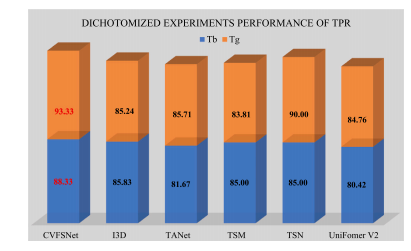

We proposed a CVFSNet based on dual-view angiographic imagesfor automatic, objective, end-to-end mTICI scoring and built a crossview fusion module, CVFM, to integrate, aggregate, and complementfeatures from different views. In the ablation experiments, we firstcompared the performance between single-view and dual-view inputs,demonstrating the necessity of dual-view image input. This may bedue to the fact that DSA imaging is projection-compressed and intracranial vessel structures are complex, leading to vessel overlap insingle-view images, which affects the model’s ability to characterizeblood flow accurately. Then, by comparing different methods of dualview feature fusion, we verified the effectiveness of the CVFM module.CVFM leverages prior positional knowledge of coronal and sagittalviews, constructs oblique sagittal features using trigonometric functionsand the Pythagorean theorem, and employs a transformer-like moduleto explore complementary relationships between coronal and sagittalfeatures, thereby building global dependencies and generating more expressive fused features, ultimately enhancing performance. In the comparative experiments, we compared our approach with some classicaland state-of-the-art video feature classification models, demonstratingsuperior performance andgood stability.In the dichotomized experiments, CVFSNet demonstrated performance exceeding 90% across all indicators, implying that CVFSNet mayhave the potential for clinical application in determining the adequacyof mTICI scores. However, our study also has limitations. Firstly, thesevideo feature classification methods that were compared in the comparative experiments only supported single-view inputs, which maydisadvantage their comparison in terms of performance. Additionally,the AmTICIS dataset constructed in this study only includes data forM1 segment stenosis, limiting its clinical applicability. In the future,we plan to expand the dataset to include more mTICI scoring datawith various vessel stenosis, such as Internal Carotid Artery (ICA), BaseArtery (BA), Anterior Cerebral Artery (ACA), and Posterior CerebralArtery (PCA) etc., thereby constructing a more comprehensive scoringdataset. Also, the sample size of AmTICIS can be further expanded byincorporating data from multiple centers to enhance its diversity.In conclusion, we propose a novel CVFSNet in this paper for automatic, objective, and end-to-end mTICI scoring. Specifically, CVFSNetemploys dual branches to simultaneously extract spatial–temporal features from coronal view and sagittal view, and these cross-view featuresare fused through a novel cross view fusion module that explores thepositional characteristics of coronal and sagittal views to fuse andgenerate a pseudo-oblique sagittal feature and deploys a transformerlike architecture to explore the correlation between different viewfeatures, ultimately constructing more representative features to enhance the scoring performance of the model. In addition, we providea newly collected and the first publicly available digital subtractionangiography image dataset with expert annotations (AmTICIS) for automatic mTICI scoring, which can effectively promote researchers toconduct studies of ischemic stroke based on DSA images and finallyhelp patients get better medical treatment. Extensive experimentationresults demonstrate the promising performance of our methods and theeffectiveness of the cross-view fusion module.

我们基于双视角血管造影图像提出了CVFSNet网络,用于实现自动、客观、端到端的脑梗死溶栓治疗改良分级(mTICI)评分,并构建了一个跨视角融合模块(CVFM),以整合、聚合和补充来自不同视角的特征。在消融实验中,我们首先比较了单视角输入和双视角输入的性能,结果表明了双视角图像输入的必要性。这可能是因为数字减影血管造影(DSA)成像是投影压缩的,且颅内血管结构复杂,导致单视角图像中出现血管重叠,从而影响了模型准确表征血流的能力。然后,通过比较不同的双视角特征融合方法,我们验证了CVFM模块的有效性。CVFM利用冠状面和矢状面的先验位置知识,使用三角函数和勾股定理构建斜矢状面特征,并采用类似Transformer的模块来探索冠状面和矢状面特征之间的互补关系,从而建立全局依赖关系,并生成更具表现力的融合特征,最终提升性能。在对比实验中,我们将我们的方法与一些经典的以及最先进的视频特征分类模型进行了比较,结果显示出我们的方法具有优越的性能和良好的稳定性。 在二分类实验中,CVFSNet在所有指标上的表现均超过了90%,这意味着CVFSNet在确定mTICI评分是否足够方面可能具有临床应用潜力。然而,我们的研究也存在局限性。首先,在对比实验中所比较的这些视频特征分类方法仅支持单视角输入,这在性能比较方面可能对它们不利。此外,本研究构建的AmTICIS数据集仅包含大脑中动脉M1段狭窄的数据,限制了其临床适用性。未来,我们计划扩展该数据集,纳入更多具有各种血管狭窄情况的mTICI评分数据,例如颈内动脉(ICA)、基底动脉(BA)、大脑前动脉(ACA)和大脑后动脉(PCA)等,从而构建一个更全面的评分数据集。同时,通过纳入多个中心的数据来进一步扩大AmTICIS的样本量,以提高其多样性。 总之,本文提出了一种新颖的CVFSNet网络,用于自动、客观、端到端的mTICI评分。具体而言,CVFSNet采用双分支同时从冠状面和矢状面提取时空特征,并且这些跨视角特征通过一个新颖的跨视角融合模块进行融合。该模块探索冠状面和矢状面的位置特征,以融合并生成伪斜矢状面特征,并部署了类似Transformer的架构来探索不同视角特征之间的相关性,最终构建出更具代表性的特征,以提升模型的评分性能。此外,我们提供了一个新收集的、首个带有专家注释的公开可用的数字减影血管造影图像数据集(AmTICIS),用于自动mTICI评分,这可以有效地推动研究人员基于DSA图像开展缺血性中风的研究,并最终帮助患者获得更好的治疗。大量的实验结果证明了我们方法的良好性能以及跨视角融合模块的有效性。

Fig. 9. TPR performance comparison in dichotomized experiments on AmTICIS, andthe best results are indicated in red

图9:在自动改良脑梗死溶栓分级评分(AmTICIS)数据集上进行的二分类实验中,真阳性率(TPR)性能的比较,最优结果以红色标出。

Table 5Performance comparison in dichotomized experiments on AmTICIS. The best results areindicated in bold

表5:在自动改良脑梗死溶栓分级评分(AmTICIS)数据集上进行的二分类实验中的性能比较。最优结果以粗体显示。